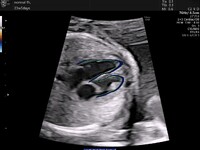

Η προγεννητική διάγνωση των συγγενών καρδιοπαθειών έχει καθιερωθεί τα τελευταία 40 χρόνια και σε εξειδικευμένα κέντρα και επιτυγχάνεται με τη μεγαλύτερη δυνατή διαγνωστική ακρίβεια. Πραγματοποιείται στις 18-20 εβδομάδες κύησης, ενώ για κυήσεις υψηλού κινδύνου ο πρώτος υπέρηχος καρδιάς εμβρύου μπορεί να πραγματοποιηθεί ήδη από τις 12-14 εβδομάδες κύησης. Από τη στιγμή που θα γίνει η διάγνωση μιας συγγενούς καρδιοπάθειας ενημερώνονται οι γονείς για την καρδιακή πάθηση, για τη διαθέσιμη θεραπεία, τη θνητότητα και τη θνησιμότητα καθώς και για την ποιότητα ζωής του παιδιού στο μέλλον. Σε επιλεγμένες περιπτώσεις υπάρχει η δυνατότητα προγεννητικής παρέμβασης. Το πλεονέκτημα της υπερηχογραφίας και διάγνωσης από το πρώτο κιόλας τρίμηνο δίνει τη δυνατότητα για έγκαιρη και ασφαλή διακοπή της κύησης σε περιπτώσεις σοβαρής, μη συμβατής με την ζωή, συγγενούς καρδιοπάθειας καθώς και επαρκή χρόνο για χρωμοσωμικό έλεγχο και γενετική συμβουλή.

Η προγεννητική διάγνωση των περισσοτέρων συγγενών καρδιοπαθειών έχει συμβάλει στην σημαντική βελτίωση της πρόγνωσης των νεογνών. Η αποφυγή διακομιδής ενός βαρέως πάσχοντος νεογνού και η μείωση του χρόνου που μεσολαβεί από την γέννηση μέχρι την πρώτη παρέμβαση βελτιώνει όχι μόνο την καρδιολογική αλλά και την νευρολογική τους πρόγνωση.